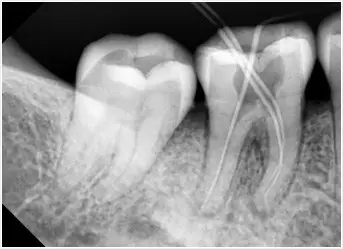

2、小牙片:就是隻能看到一兩(liang) 顆牙齒牙根情況的那種牙片,一般主要用於(yu) 查看牙根管、牙根等情況。價(jia) 格一般在幾十上百元左右,是牙片中比較便宜的一種。如下圖:

根管治療拍片